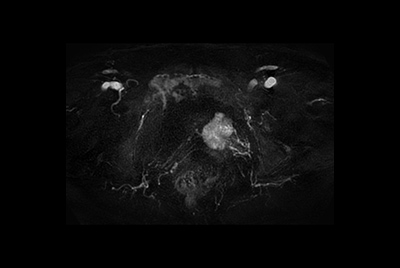

Pancreas nodule – Free breathing